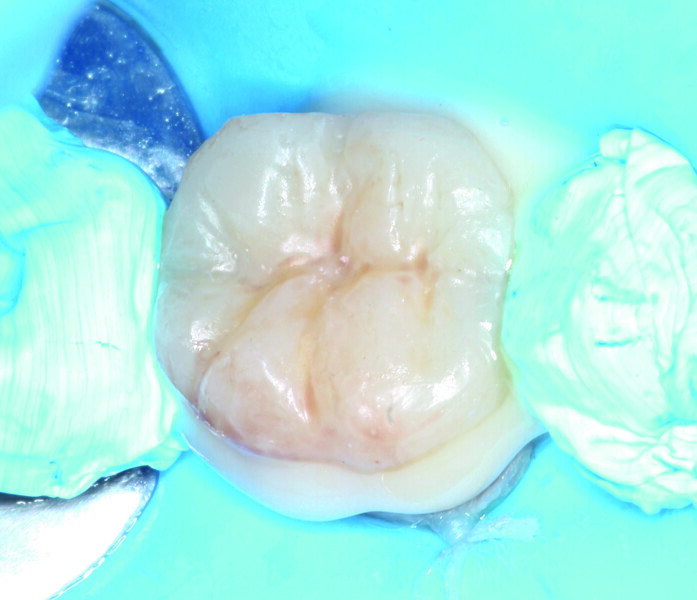

Fig. 5: Completed filling with Grandio.

The direct restoration of tooth #45 used the light-polymerising, nano-hybrid composite Grandio. We rebuilt the distal wall, initially with Grandio, in order to convert the Class II configuration into a Class I cavity design (Fig. 4). This strategy was chosen to make the handling of the proximal and occlusal filling easier. To achieve this, a regular incremental layering technique was used (Fig. 5). Finally, we performed finishing and polishing of the occlusal surface of tooth #45.